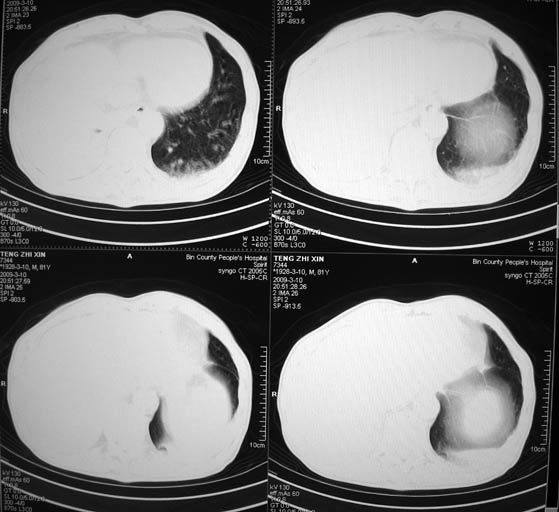

标题: CT18642:男,81岁,发热待查。

男,81岁,发热待查,右侧是占位还是膈疝?

1)考虑右肺下叶中央型肺癌并左肺转移。2)两肺上叶结核(陈旧性)。3)双侧胸腔积液。4)腹水。

右肺癌并双肺及胸膜转移。

右中央型肺癌并双肺及胸膜、肝脏转移

支持,肿块巨大,内有钙化\\坏死,肺肉瘤要考虑

很明显的排除膈疝。考虑右肺中央型肺癌,建议增强。胸腔恶性胸水。